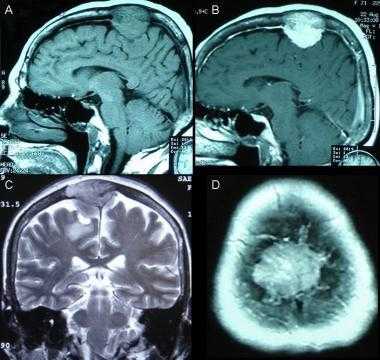

(Слева) МРТ, Т2-ВИ, корональный срез: у мужчины 47 лет определяется внемозговое образование однородной структуры с четкими контурами с минимальным отеком.

(Справа) МРТ, постконтрастное Т1 -ВИ, аксиальный срез: у этого же пациента визуализируется интенсивное относительно однородное контрастное усиление. Обратите внимание на компрессию треугольника левого бокового желудочка. Несмотря на отсутствие агрессивных рентгенологических признаков при хирургической резекции и гистологическом исследовании была диагностирована злокачественная Менингиома grade III. Для окончательного установления гистологического типа и степени злокачественности менингиомы необходима биопсия.

(Слева) МРТ, высокоразрешающее Т2-ВИ, аксиальный срез: у этого же пациента хорошо визуализируется гипоинтенсивное объемное образование с кистозными компонентами и четкими контурами. Гиподенсность указывает на высокое содержание клеточного матрикса в опухоли.

(Справа) МРТ, постконтрастное Т1-ВИ SPGR, корональный срез: контрастное усиление солидных компонентов опухоли. Было выполнено хирургическое удаление, был поставлен гистологический диагноз смеси светлоклеточного (grade II) и склерозирующего вариантов менингиомы.